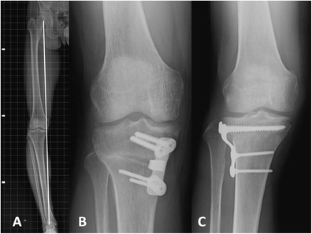

Fig. 1